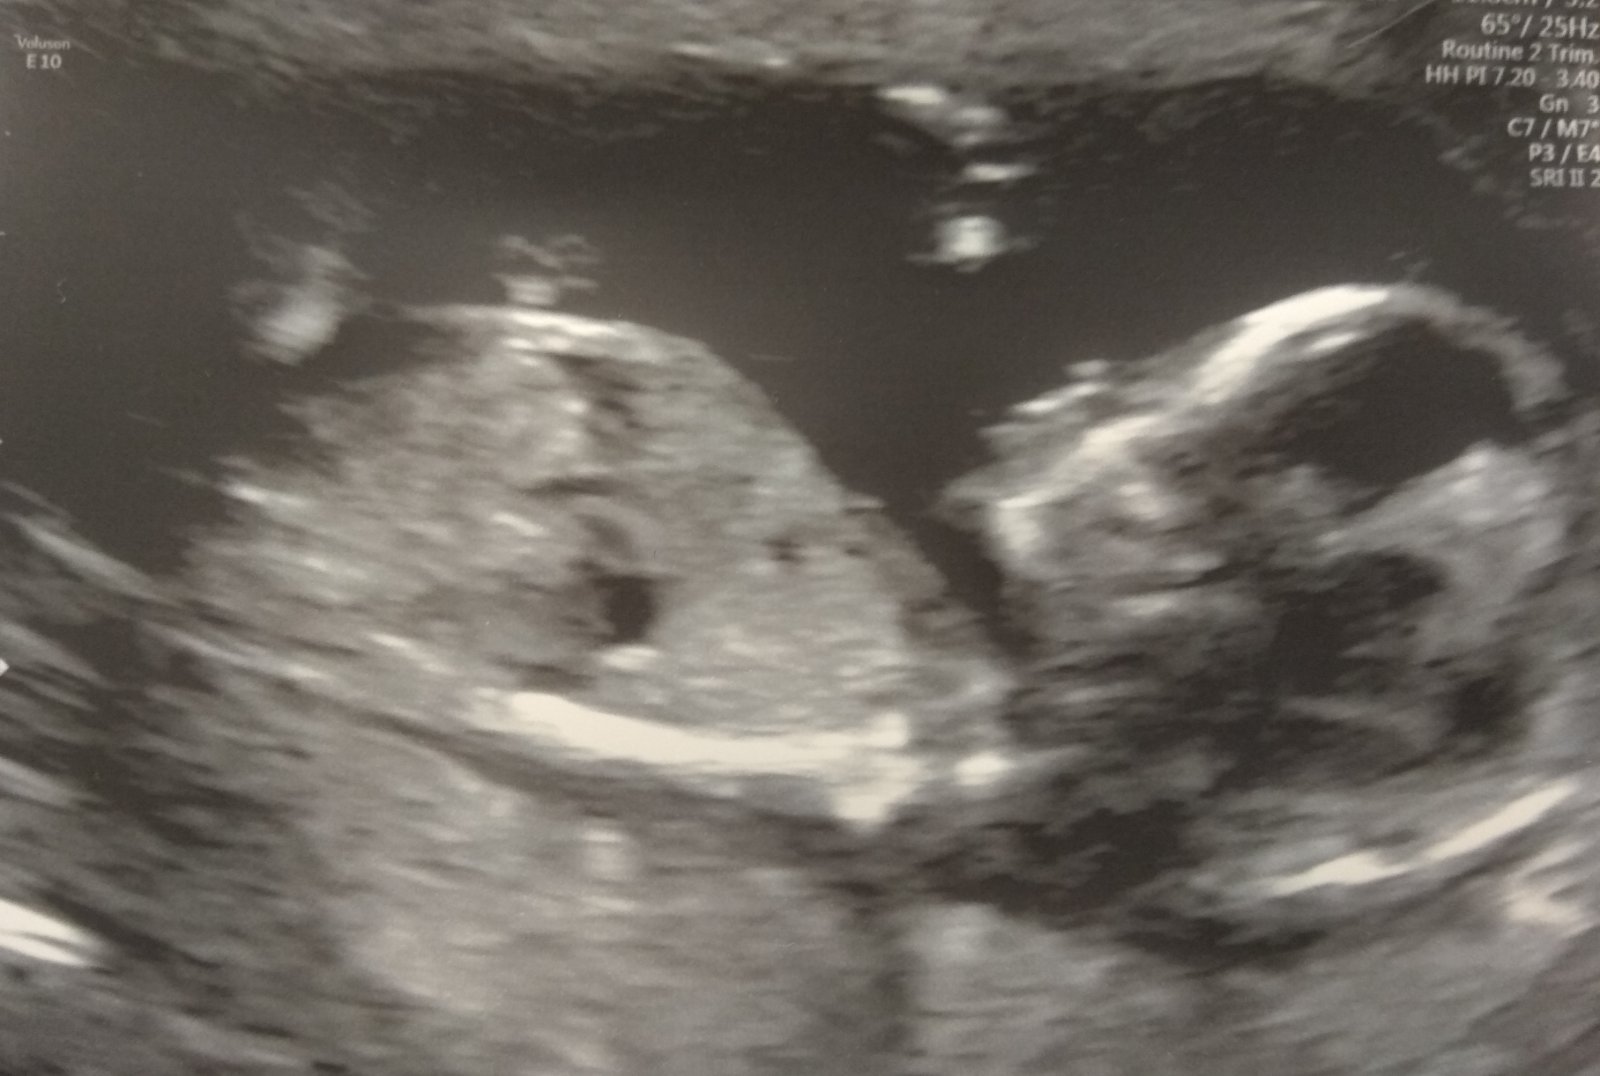

Zítra bych měla začínat třetí měsíc... 🍀 Začíná mi růst to spodní břicho, takže jsem nateklá a bolavá. Vorvaň hadr 🐧 Jelikož vaření nestálo poslední dobou za nic, začla jsem chodit pro obědy... Takže piraňa má stálý přísun a chlap taky... 😇 Upřímně ho dost obdivuju, protože jsem zvyklá být pořád v jednom kole a teď to nejde a jsem z toho špatná (takže brečím... už je to tady 😇 ) Hafani se mnou hodně léhají, jsou to zlatíčka terapeutí, co ti budu povídat 🙂 Kontrolu větší mám 19.12., to bych měla být 10+5. Tak se těším a doufám, že se dozvím víc 🙂

@lucizaji Taky jsem párkrát musela psát po mobilu, protože přes pc ne a ne to odeslat 🙂 O třetí světové já radši mluvit nebudu, protože jí máme stále doma... 😀 Tak snad bude Sofi zase brzo dobře 🙂 Jo, je fakt, že takový nadstres jsem měla srpen září a jak to pak dopadlo... Těla ví, kdy je jejich nejlepší čas... Vánoce jsme zdárně užili, v jídle jsem se neupejpala a připadám si teď jako vzducholoď... Kontrola dopadla před Vánoci skvěle, jen gyndařka kroutila hlavou, že se jí zdá o týden větší (což je nemožné, vím kdy jsem ovulovala), tak uvidíme 3.1. na genetice. Pak už to ofiko chci říct v práci... Trápí mě hlavně večerní nevolnosti a sem tam to slzavé údolí... Chlap to zatím dává 😀 Pořídila jsem si angel sounds a nelituju. Sem tam si zkontroluju ozvy mimča... Je to nádhera, poprvý jsem to obrečela 😇 Včera poslouchaly neteřinky a byly unešené, zkoumaly i appku v mobilu.. 🙂 S těma dětma to má takové zvlášní kouzlo 🙂